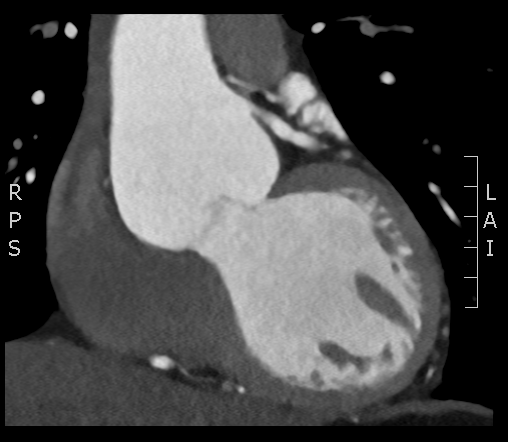

A CTCA is performed: